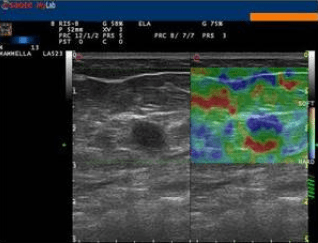

Presso lo studio di ecografia di Campobasso si esegue l'elastosonografia, o elastografia, l'ultima nata tra le applicazioni nel campo della diagnostica ad ultrasuoni. Essa si affianca alle applicazioni tradizionali dell'ecografia, come l'ecocolordoppler, aumentandone l'efficacia diagnostica, in quanto in grado di fornire informazioni sul grado di elasticità o di durezza di un tessuto o di un nodulo, rispetto ai tessuti sani circostanti.

Essa si basa sul principio secondo cui la compressione del tessuto in esame, esercitata dalla sonda ecografica, produce una distorsione, minore nei tessuti duri, quali quelli neoplastici o fibrotici, e maggiore in quelli soffici.